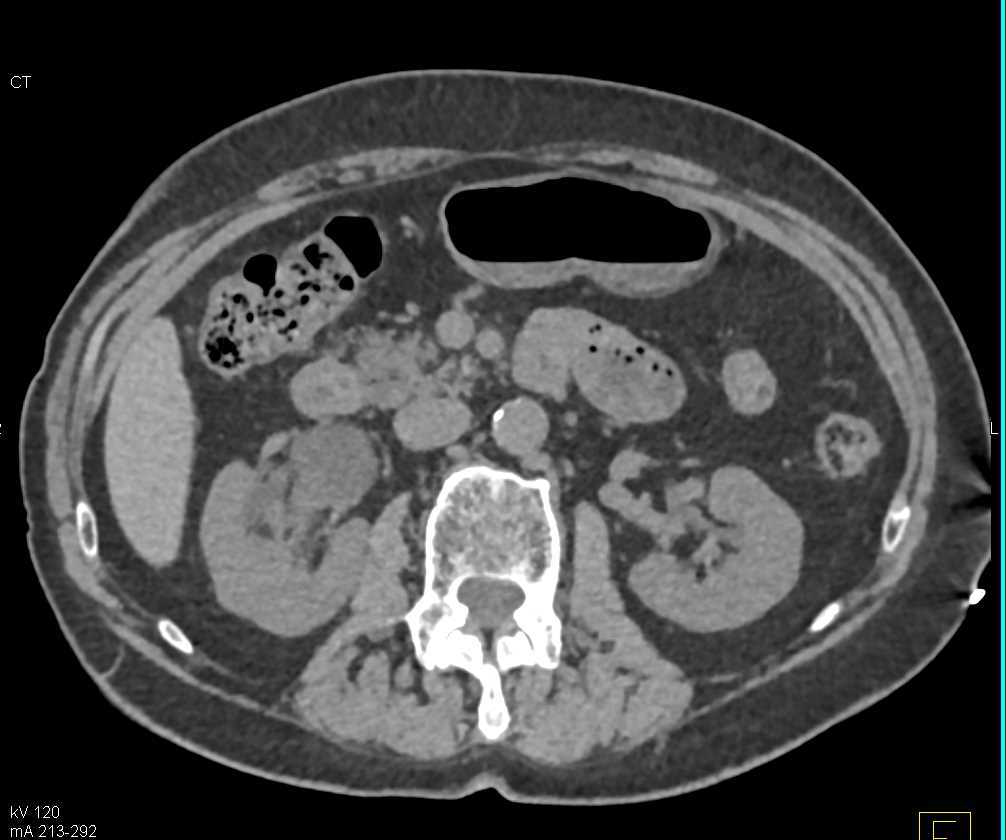

Renal Cell Carcinoma Involves the Renal Vein and Inferior Vena Cava (IVC)